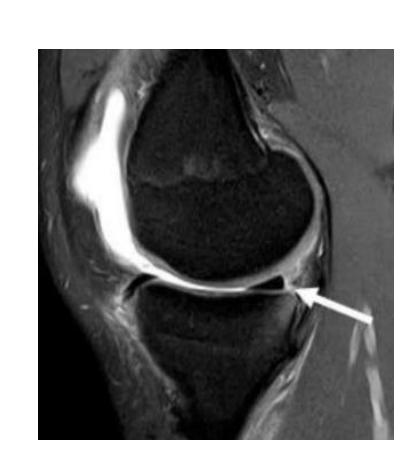

What pathology is seen in this MRI of an 18-year-old male who twisted his knee?

- Posterior horn meniscal tear

- Bucket-handle meniscal tear

What is the significance of the double PCL sign?

- Indicates bucket-handle meniscal tear

What does the white arrow indicate in this image?

- Posterior meniscus horn

What is the diagnosis shown in these images?

- Posterior meniscus horn tear